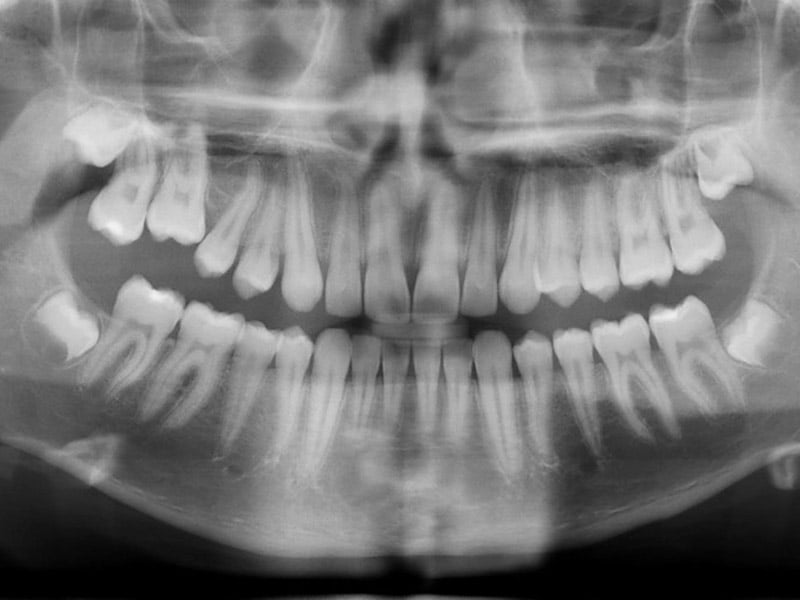

Los rayos X dentales (también llamados radiografías) son una parte importante del tratamiento dental porque pueden detectar daños en los dientes y las encías que no son evidentes durante un examen visual de rutina.

Por ejemplo, las radiografías pueden mostrar la condición de tus dientes, sus raíces, el posicionamiento de la mandíbula y la composición general de los huesos de tu cara. Las radiografías pueden ayudar a tu dentista a determinar la presencia o el grado de enfermedad periodontal (en las encías), caries, abscesos y varios bultos, como quistes y tumores.